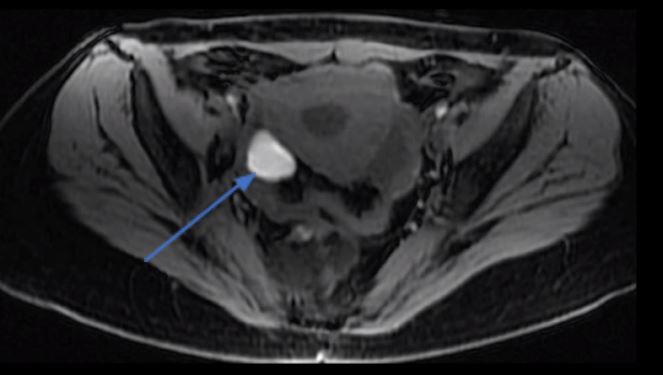

Endometriose no ovário

A endometriose no ovário se caracteriza pela presença de um cisto ovariano, chamado endometrioma.

O conteúdo dos endometriomas é sangue proveniente dos focos de endometriose, que todo mês determinam sangramento para o interior da cavidade do cisto aumentando o tamanho do cisto.

A hemoglobina contida no interior destes cistos está mais degradada que a hemoglobina proveniente de sangramentos mais recentes, como por exemplo nos cistos de ovulação (cistos hemorrágicos), possibilitando desta forma o diagnóstico pelos métodos de imagem.

Ressonância magnética demonstrando um endometrioma no ovário direito (seta azul)

Endometrioma caracterizado no ultrassom transvaginal com preparo intestinal